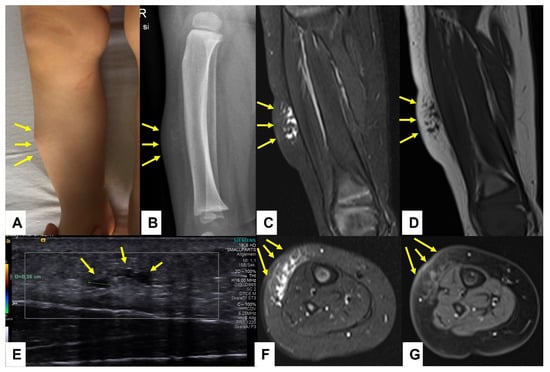

Figure 7.

This composite figure illustrates a subcutaneous lump on the right lower leg of a 12-month-old girl (A)—(arrows). X-ray at presentation showed a cloudy pretibial soft-tissue lesion with no osseous deformities (B)—(arrows). Ultrasound imaging of the lesion was unspecific but showed some small cystic areas in the deep dermis (E)—(arrows). MR imaging at the age of 13 months showed a strict epifascial tubulo-cystic lesion in the subcutaneous tissue in the anterolateral area without contrast enhancement (C,D,F,G)—(arrows).

In all 47 cases, the MRI showed that the lesions consisted of multicystic or tubular vascular areas, and the diagnosis of low-flow SVM was considered in all cases. Figure 7 and Figure 8 illustrate the findings in one patient with a confirmed LM who presented with a lesion located over the pretibial area clinically mimicking SGA.